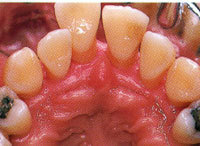

▼STEP5 術後

歯周炎が改善し引き締まった歯ぐきになりました。

治療後のよい状態を維持するために、歯科医院での定期的なメインテナンスと毎日のセルフケアが大切です。

ブラッシングによるプラークコントロールや、スケーリング・ルートプレーニングおよび歯周外科処置によって、 歯周炎が改善し引き締まった歯ぐきになりました。